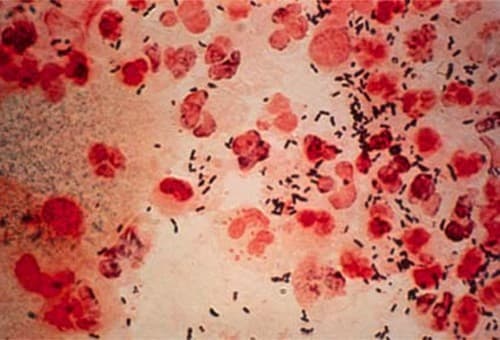

Sau thời gian ủ bệnh, bệnh lậu sẽ biểu hiện ra bên ngoài bằng các triệu chứng như: Người bệnh thấy hơi ngứa, nhồn nhột ở đường tiểu; sau vài giờ thì tiết ra chất dịch trong, đục dần rồi thành mủ, màu vàng hơi trắng. Khi đi tiểu, người bệnh có cảm giác nóng rát, tiểu gắt, tiểu buốt, mủ chảy ngày càng nhiều. Trường hợp nặng có thể tiểu ra máu. Toàn thân có thể sốt nhẹ, mệt mỏi, đau mình mẩy…

Ở giai đoạn này, vi khuẩn từ niệu đạo trước, xâm nhập sâu dần đến các tuyến và niệu đạo sau rồi tiếp tục sinh sôi phát triển. Các triệu chứng trên sẽ mất dần, chỉ còn tiểu ra giọt đục vào buổi sáng và tăng lên khi lao động nặng, thức khuya, uống rượu bia…